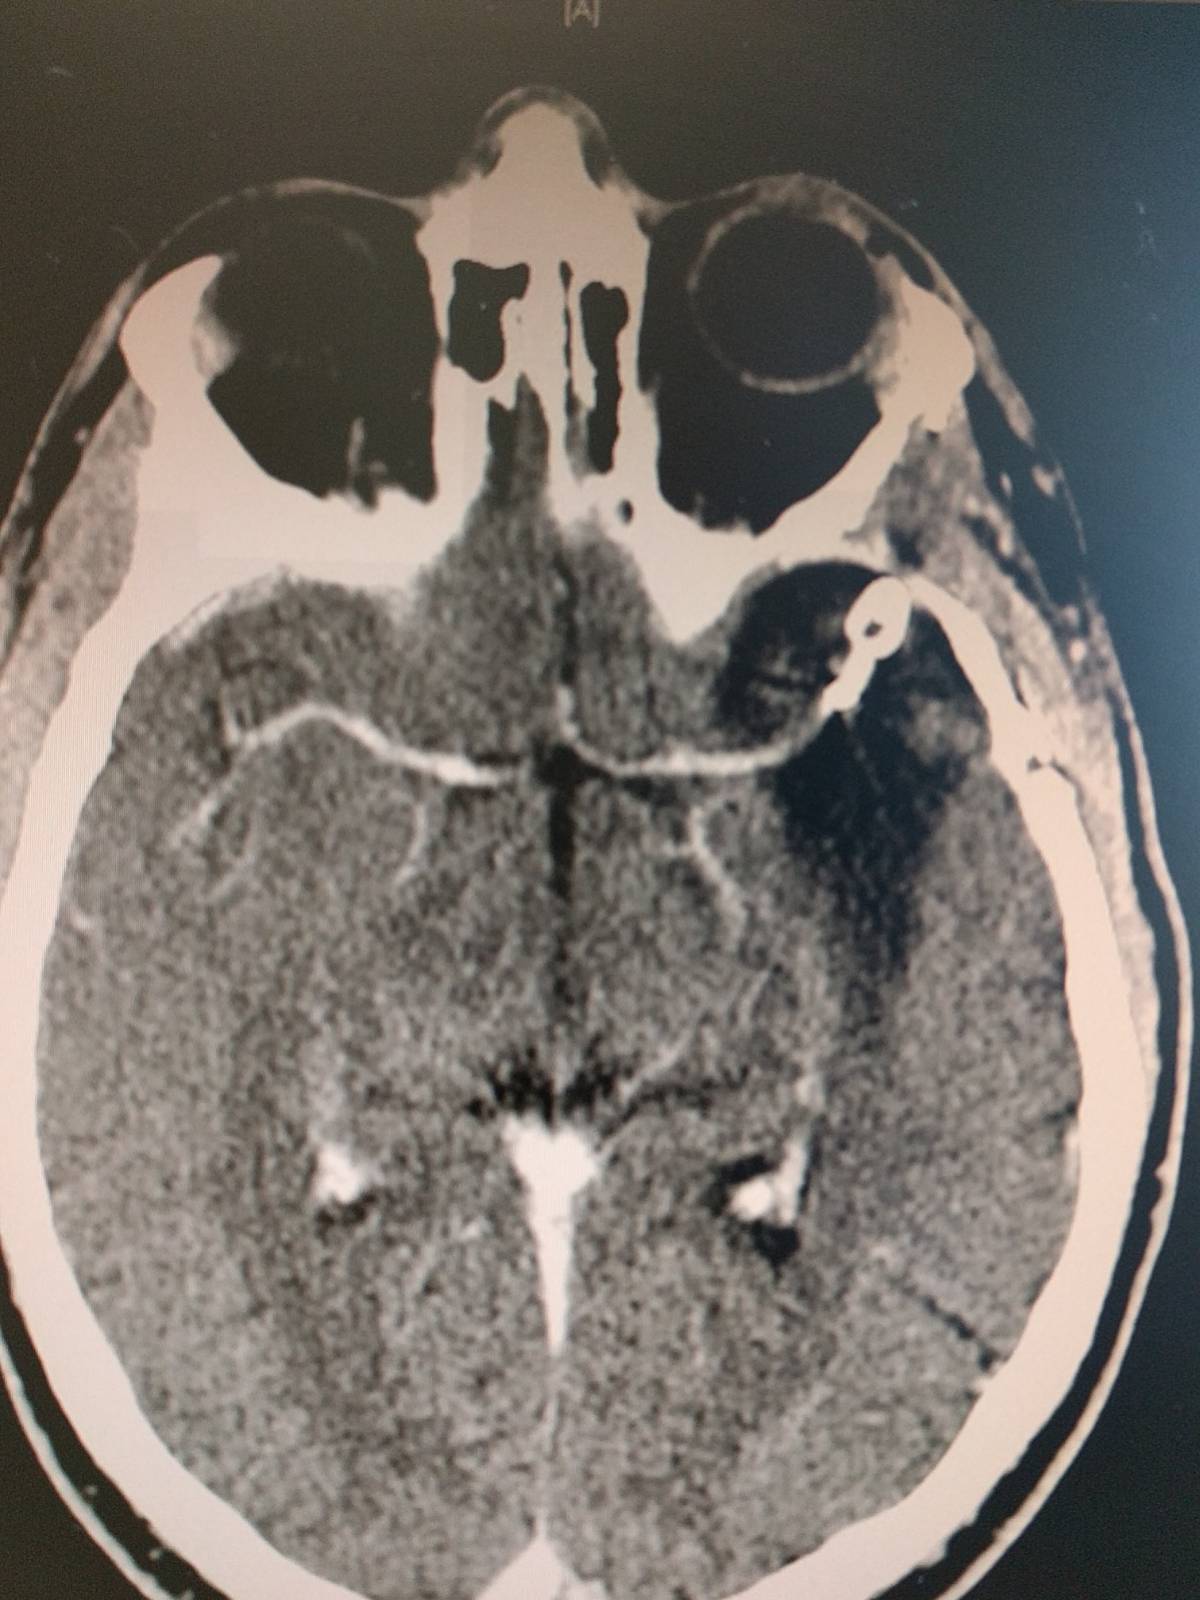

I want to celebrate Exactly 10 years ago, a had a ruptured brain aneurysm.

On December 14th, it ruptured after no previous side effects, indicators, migraines or warnings. Within minutes, I lost all senses and no idea what was happening.

8 days later, I woke up from a coma. Thanks to Dr. Kim, I was a survivor. A brilliant surgeon, researcher and dedicated to understanding what actually causes aneurysms and how they can determine which ones will burst.

I had a lot of brain damage and now a permanent titanium clip in my head. I never gave up and to this day, I continually work to improve my speech which was the area that was damaged behind my left eye. It is amazing on what the brain can do and shift functions when trauma occurs.